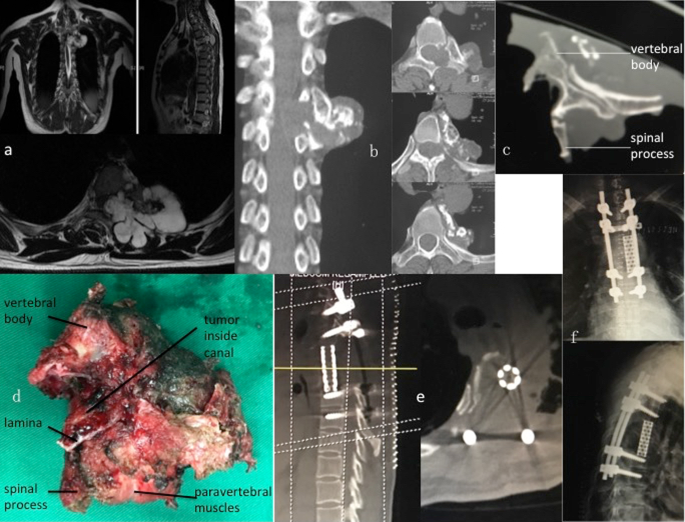

Surgery to remove tumors (benign or cancerous) that grow inside or around the spine.

The tumor is carefully removed while protecting nerves and the spinal cord. Sometimes rods or screws are added for stability.

Tumor Removal

The tumor is carefully removed while protecting nerves and the spinal cord.

Stabilization

Rods or screws are added for stability when needed.